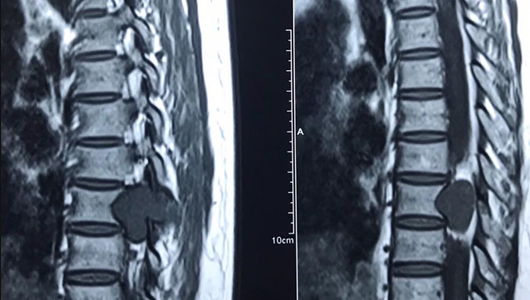

4.5. Cộng hưởng từ hạt nhân: